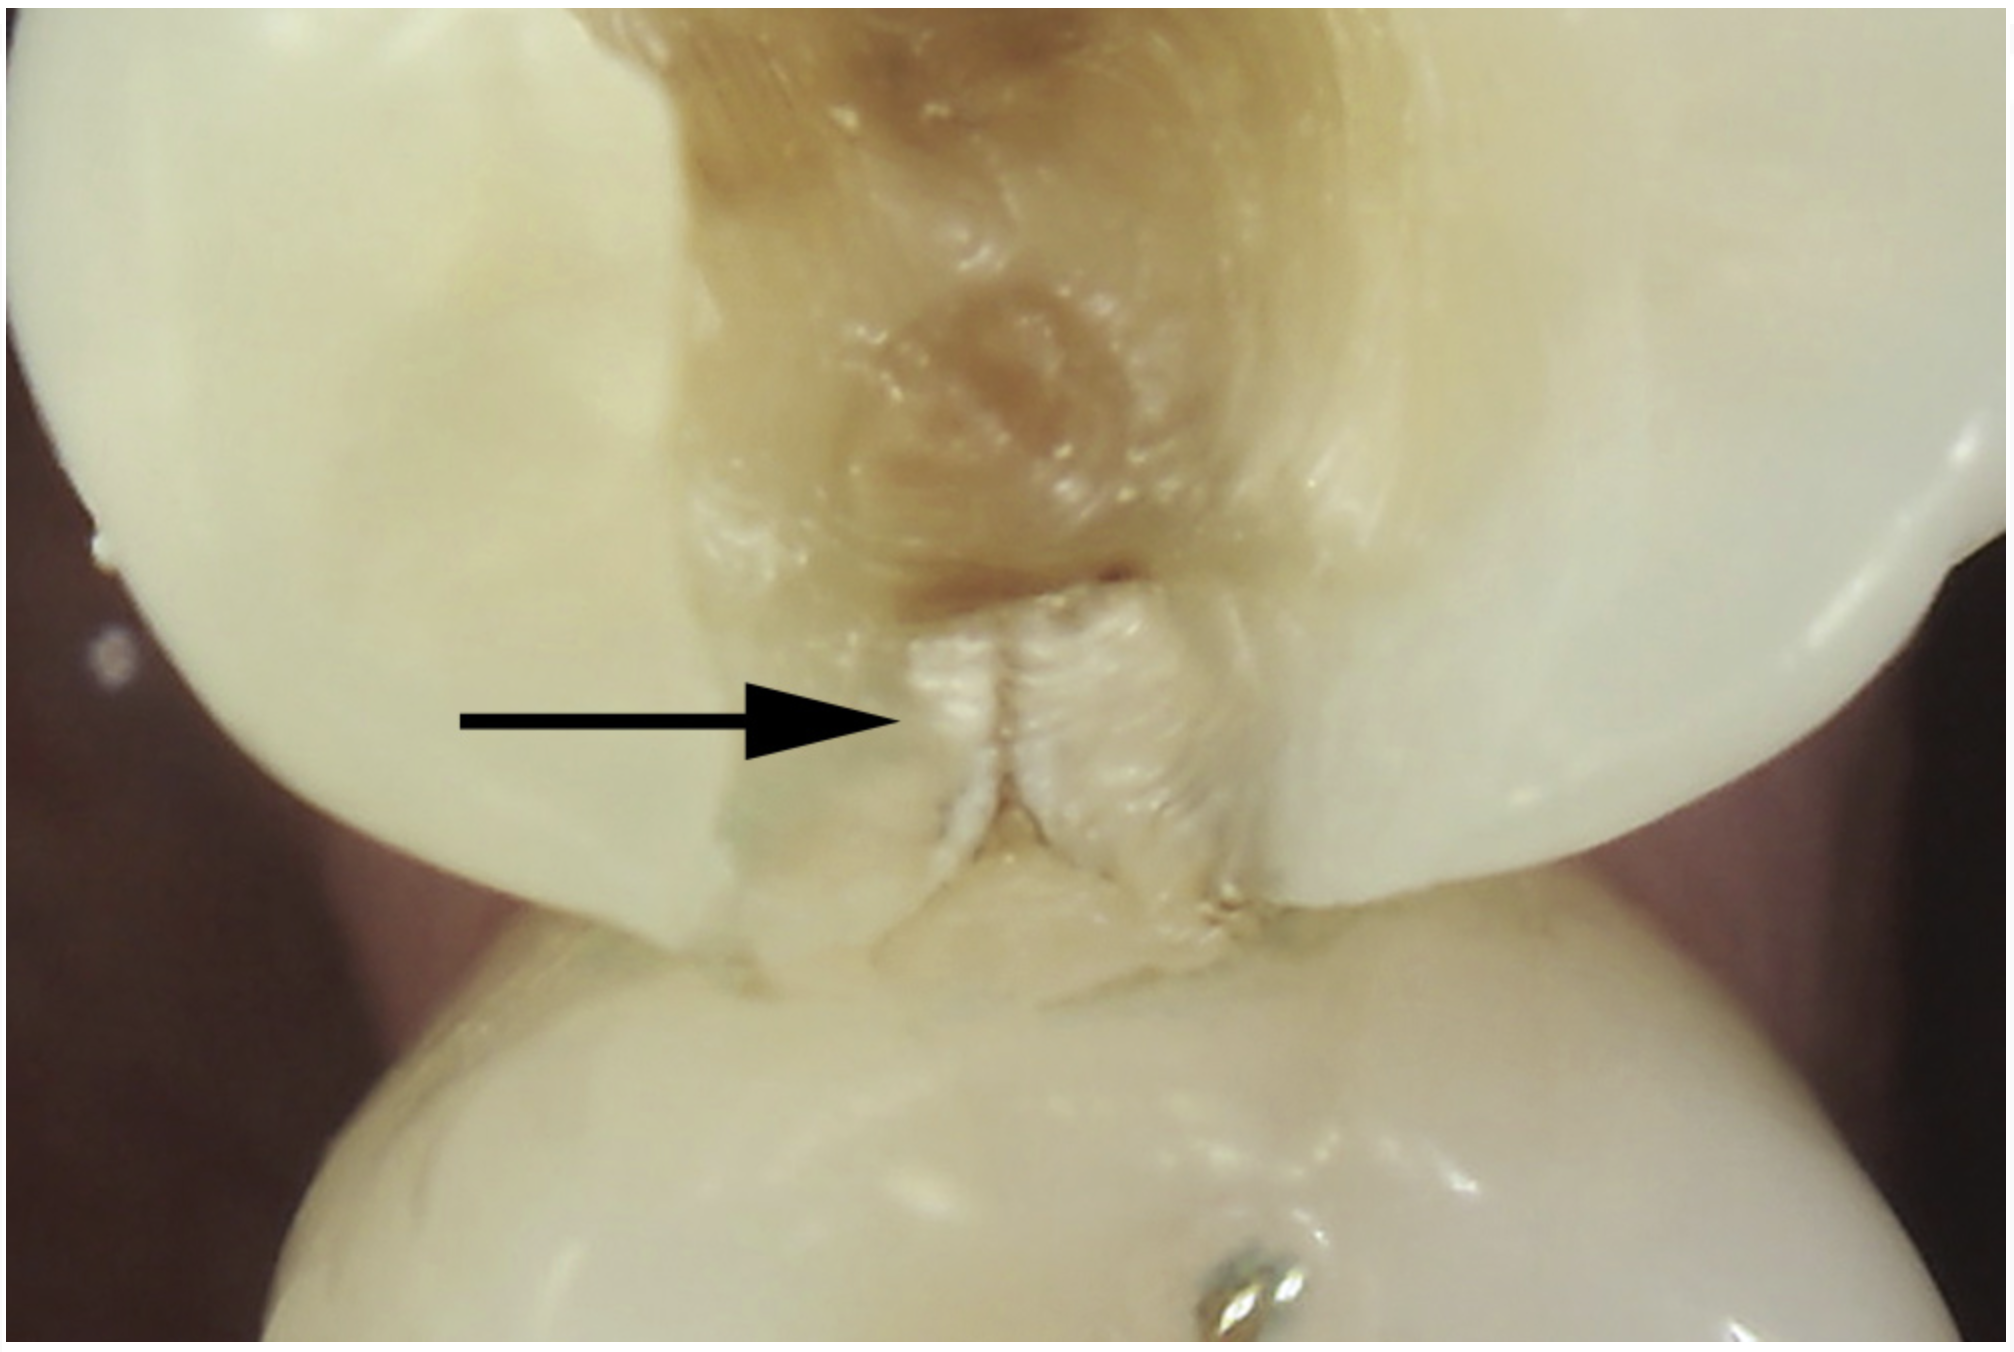

Fig 3. Transillumination of an asymptomatic maxillary left second premolar blocked by an enamel marginal ridge crack (arrow) (mesio-occlusal view).

Figure 3

The use of fiber-optic transillumination for crack diagnosis is well documented in the literature.1-3,5,6,8-10,12,15-17,21-23 Teeth with significant cracks transilluminated with a fiber-optic light source will show a well-defined demarcation of blocked illumination at the crack lines, whereas structurally sound teeth will dissipate the light gradually throughout the tooth structure (Figure 3).22 While a variety of transillumination devices have been used to reveal cracks, pen-sized cordless units with a highly collimated light source and that are specifically manufactured for this purpose are ideal for this diagnostic technique. This is mainly because they emit the proper amount of light intensity to highlight cracks, and viewing can be done directly with the eye without using a protective device.22